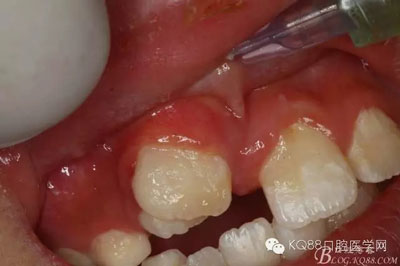

圖4.局部粘膜先涂表麻膏

圖5.唇側(cè)無(wú)痛浸潤(rùn)麻醉

圖6.腭側(cè)無(wú)痛浸潤(rùn)麻醉